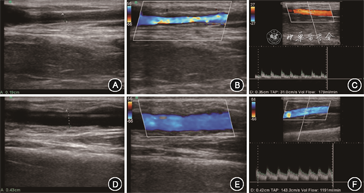

临床判断为AVF成熟不良的患者采用彩色多普勒超声(索诺声M-Turbo,线阵探头)进一步检查,评估AVF动脉流入道、吻合口、静脉穿刺段和静脉流出道的血管直径、血流通畅情况及血流动力学参数、判断病变部位并分析AVF成熟不良的原因(图1A~C)。

术后通过超声再次评估病变处血管直径、血流通畅情况及血流量(图1D~F),技术成功的判断标准为:球囊扩张后管腔残余狭窄<30%;临床成功的判断标准为:术后连续4周可以完成患者的双针穿刺血液透析。